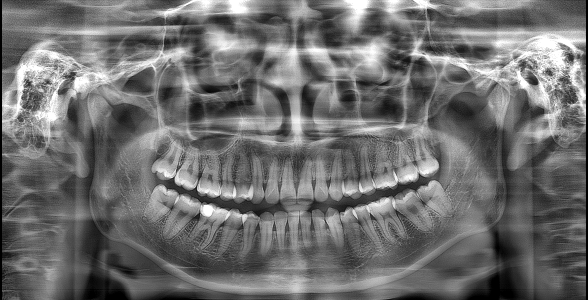

▲“ "The Effect of 'PD' Technology in Panoramic Images"

▲Advantages of "PD" Technology: Deep Restoration of Image Details